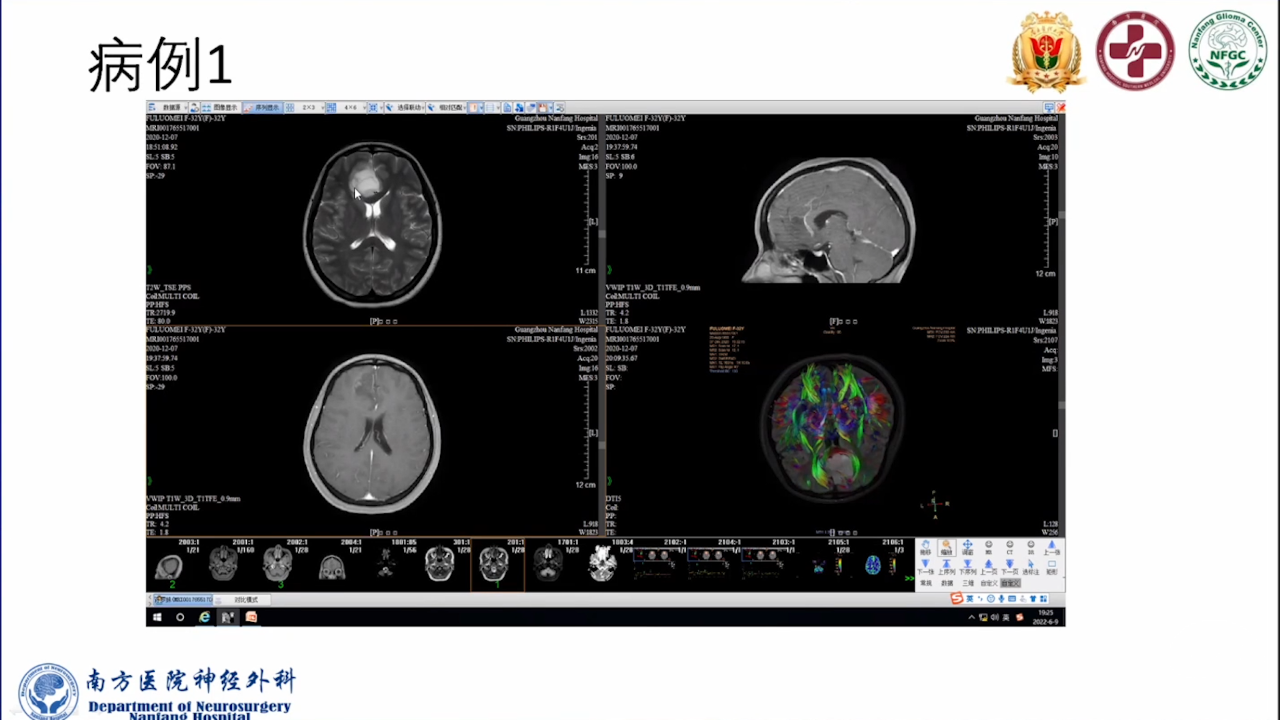

巨大的脑胶质瘤往往破坏皮层功能,推挤白质纤维束,包裹重要供血动脉,正常解剖结构移位。手术切除病变可以挽救患者生命。如果术中确保重要动脉不损伤,并在术前纤维束成像指导下按照解剖结构标志尽可能保留神经纤维束,患者将在获得辅助治疗机会的同时,神经功能也得以逐步恢复,更有利于脑胶质瘤的预后。